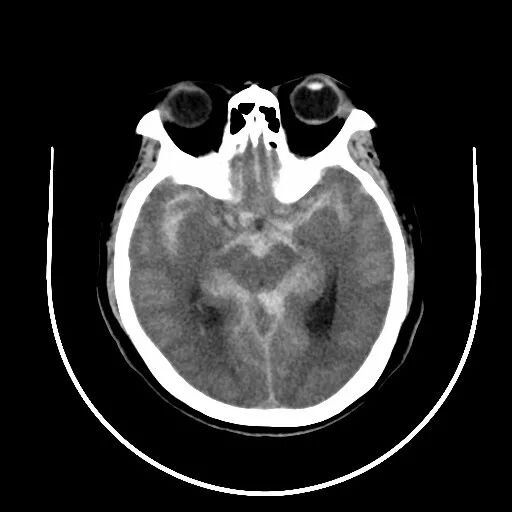

术前CT:鞍上池及双侧外侧裂见高密度影,蛛网膜下腔出血。(图1)

图3-1. 患者入院后头颅CT提示蛛网膜下腔出血,以脑干前方为主,提示后循环动脉瘤破裂出血可能。